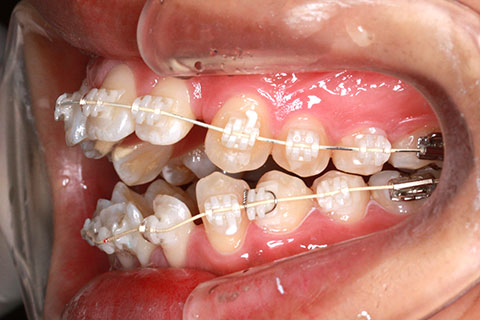

症例1

治療中

年齢・性別

23歳女性

治療期間

1年4ヶ月

抜歯

なし

治療費

80万(税込)

備考

マルチブラケットを用いた矯正治療

治療内容

前歯の開口を顎間ゴムにて改善

施術の副作用(リスク)

舌の癖や鼻疾患がある時は、後戻りを起こすことがあります。